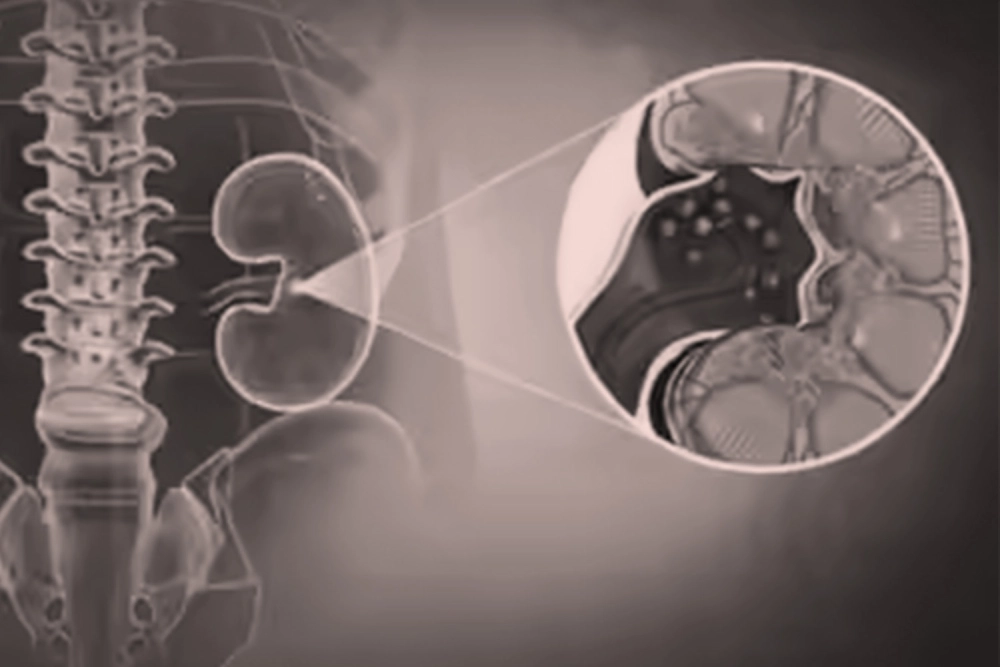

Kidney Stones & Stone Disease

Kidney and ureteric stones can be incredibly painful and disruptive of daily life appropriately managed, however, treatment can be targeted, safe, and less invasive than most imagine.

Patients looking for a Kidney Stone Specialist in Mumbai trust Dr. Jeena KR’s evidence-based care. She applies modern medicine and technology to treat and prevent stone disease. She provides a comprehensive patient evaluation including imaging (CT, Ultrasound) and metabolic work up, which is vital in identifying stone size, location, and potential medical causes.

She employs techniques such as Lithotripsy (either laser or pneumatic assisted), Flexible and Semi-rigid Endoscopy (URS, fURS / RIRS) and Percutaneous Nephrolithotomy (PCNL). Each of these techniques is a minimally invasive procedure where stones are removed or broken, using small instruments. In most cases, these techniques have less recovery time and fewer complications than alternatives.